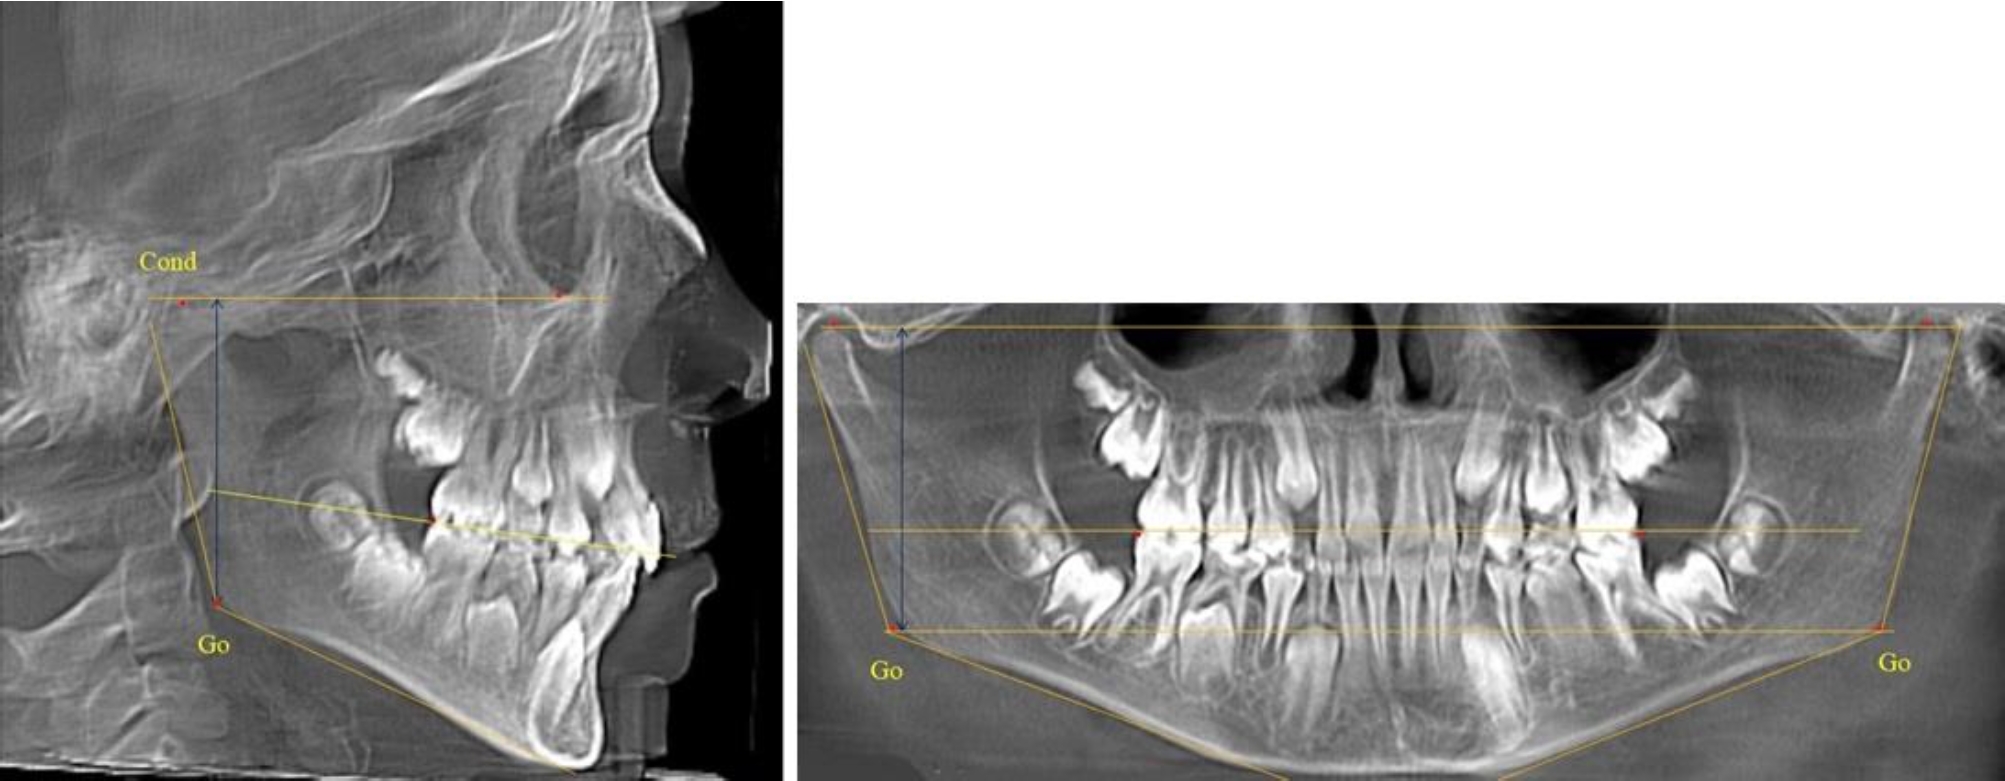

В 5-й группе были проанализированы 14 комплектов рентгенограмм, что составило (13,21 ± 3,29) % от общего числа. На всех рентгенограммах отмечен очередной этап подъема высоты прикуса, обусловленный прорезыванием вторых постоянных моляров. Окклюзионная линия делила ветвь на два отдела (рис. 5).

Рис. 5. ТРГ и ОПТГ пациента после смены молочных зубов и прорезывания вторых постоянных моляров

Высота ветви у детей 5-й группы составляла (62,87 ± 3,62) мм, что было достоверно больше, чем у детей других групп (р ˂ 0,05). При этом высота верхней окклюзионно-суставной части была (40,23 ± 2,01) мм, а нижней – (22,64 ± 1,78) мм. Высота верхней части была вдвое больше нижней, что и определяло особенности соразмерности частей ветви нижней челюсти в анализируемый возрастной период.

Относительные показатели соразмерности частей ветви нижней челюсти показали, что отношение высоты верхней части ветви к нижней в среднем составляло 1,78 ± 0,18. Отношение общей высоты ветви к верхней ее части составляло 1,56 ± 0,12, а отношение общей высоты ветви к нижней ее части было 2,78 ± 0,14, что и определяло особенности соразмерности частей ветви нижней челюсти в анализируемый возрастной период.